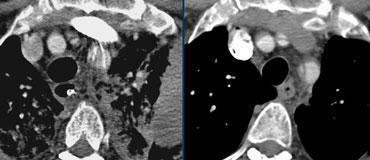

Bóc tách type A lan vào các động mạch thân cánh tay đầu. TRÁI: Không thấy khi tiêm ở tay trái. PHẢI: Cùng bệnh nhân khi tiêm ở tay phải.

Có thể giảm đáng kể xảo ảnh và do đó giảm thiểu các bẫy chẩn đoán bằng cách:

- Tiêm thuốc cản quang ở tay PHẢI: không có thuốc cản quang đi qua phía trước các nhánh bên của quai động mạch chủ, tránh làm méo hình ảnh vạt nội mạc (hình minh họa)

- Bơm đuổi bằng nước muối sinh lý (chỉ có thuốc cản quang trong các lòng mạch cần quan tâm)

- Chụp đồng bộ điện tâm đồ (giảm xảo ảnh chuyển động giả vạt nội mạc)